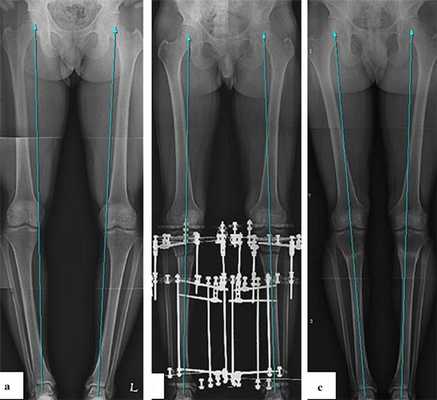

Для планирования операции по коррекции деформации нижних конечностей вам потребуется сделать рентгенограммы обеих нижних конечностей стоя с нагрузкой весом тела. Это позволит определить расположение анатомических и механических осей, обнаружить вершину деформации, произвести расчёт необходимой коррекции и выбрать оптимальный метод последующей фиксации остеотомии.

Часто встречающаяся ситуация - вальгусная деформация ног + наружная ротация + укорочение левого бедра 2 см. Слева деформация более выражена, поскольку деформированы были и бедро, и голень. Провели двухэтапную коррекцию. 1 этап - левое бедро, 2 этап - обе голени. Genu valgum (в отличие от genu varum) часто обусловлена деформацией бедренных костей. Поэтому для определения объема операции обязательно нужен рентген ног по всей длине.